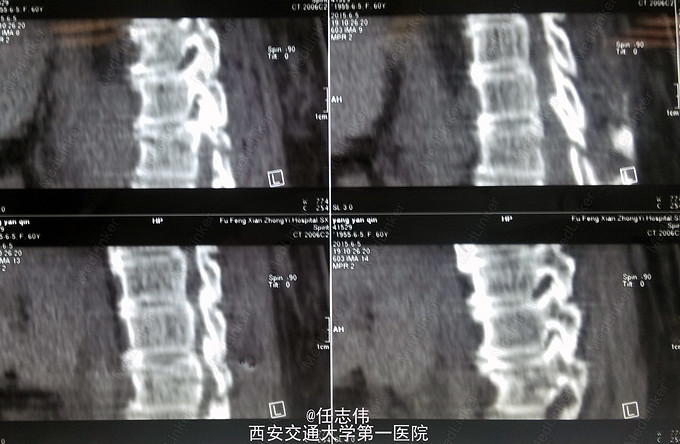

患者女性,60岁,车祸伤致双下肢感觉活动不能8h入院。 8小时前坐农用车时,被横杆撞倒腰部,摔下后感觉胸背部疼痛,双下肢活动不能,伴有短暂昏迷病史。遂来我院就诊。

左侧胸壁广泛压痛,呼吸急促。专科查体:胸背部广泛压痛,自腹股沟平面以下感觉、运动消失,腹壁反射消失,肛门反射消失,巴氏征阴性。双上肢感觉运动正常,骨盆分离挤压试验阴性。

诊断:1.胸11椎体骨折伴截瘫(Frankel A级)2.闭合性胸部损伤,肺挫伤,多发肋骨骨折,双侧胸腔积液 处理:1.急诊入院告病危,心电血氧监护;2.予以甲强龙冲击治疗;3.次日复查胸部CT,查看肺部损伤情况及胸腔积液,后予以右侧放置闭式引流。患者氧合不稳定,2日后复查胸片胸腔积液减少,予以行后路减压内固定融合术。 手术:术中见局部软组织损伤严重,胸11-12棘上、棘间韧带断裂,胸10、11、12双侧关节突有骨折移位,胸11椎板骨折,胸11左侧不能置入椎弓根螺钉,遂行单纯固定。脊髓局部挫伤明显,并有硬膜破损,予以处理。